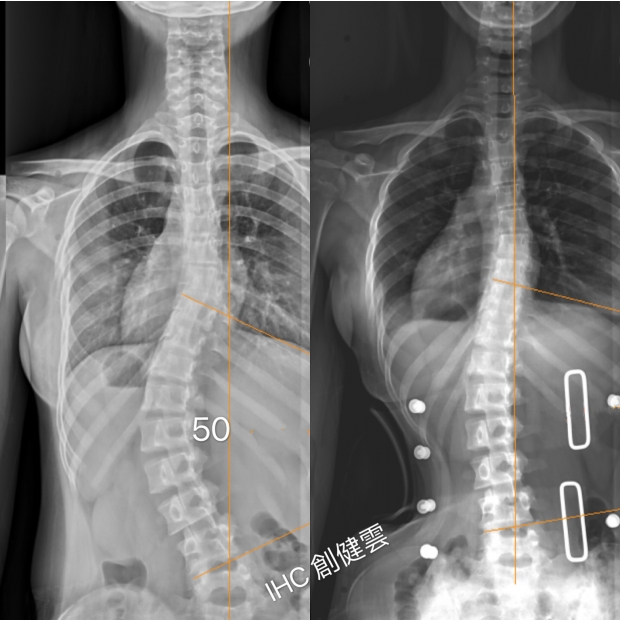

16歲重度脊椎側彎女孩

胸腰彎50度